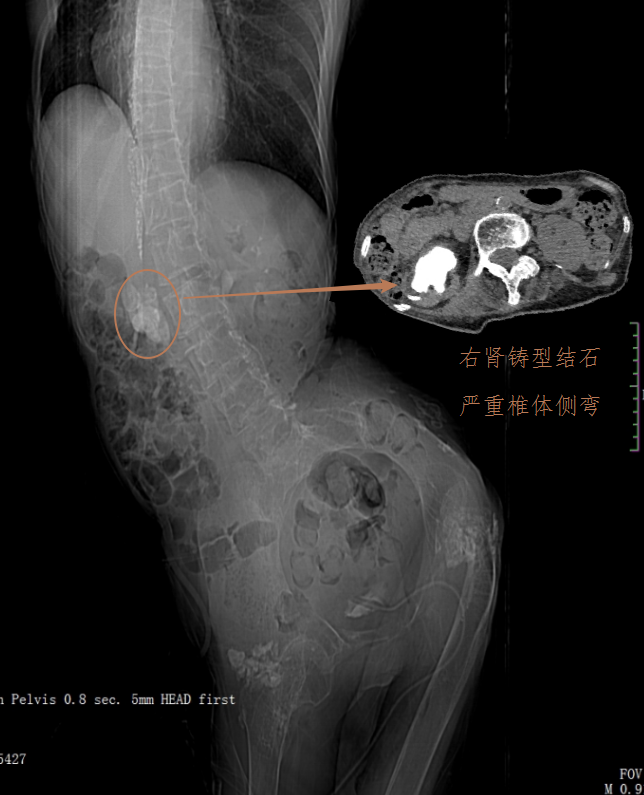

贺奶奶腹部CT图像(肾脏铸型结石,严重的身体畸形)

入院时,医生发现,贺奶奶胸部以下完全没有知觉,由于没有神经支配,腹部和下肢肌肉萎缩僵直,脊柱严重侧弯畸形,身体多处皮肤压疮,深达骨头。同时,这50多年间,老人出现反复的泌尿系统感染,经历2次膀胱切开取石和胆囊切除,但是右边肾脏里面还有一颗巨大的铸型结石却一直没有得到救治)。